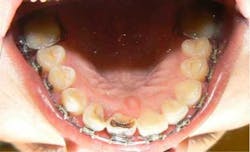

She came to me for an orthodontic consultation. She was 24 years old and hoping to marry her then-boyfriend at some point, but she didn't like her smile; she felt it was unattractive. So we gathered her orthodontic records and pointed out to her that it appeared she had either a supernumerary tooth or over-retained primary tooth between her upper centrals. Along with this, she also had some minor crowding on her lower teeth. She had a Class I molar relationship that I hoped to maintain.

Month 0-3 I like to start all my orthodontic cases off with a light round nickel titanium wire such as an 014N or 012N. While in this wire, I used some elastomeric chain to help align and rotate the teeth.Month 4-10 I continued to level the teeth and begin to reposition brackets on a 18X25 heat-activated NiTi wire based on a panoramic X-ray that I like to take to help me with root positioning.Month 11-16 Progress to a stainless steel 19x25 wire for more tooth torque and better bracket engagement.Month 16-18 Finishing on a 018SS. I don’t have much wire-bending skills, so I mostly move brackets and am capable of only some simple step bends.